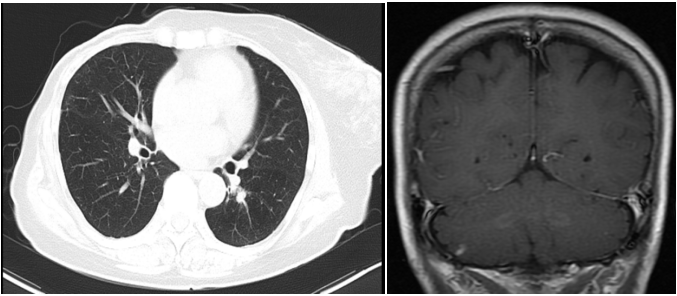

患者3年余前(2018.11)行右乳肿块穿刺活检,病理提示:右乳浸润性导管癌Ⅲ级,Ki-67(40%,+),ER(-),PR(-),HER2(3+)。PET-CT提示:右乳占位,考虑乳癌可能,伴右侧腋窝淋巴结转移,两肺及肝左叶多发转移,胸腰椎多发骨转移。头颅MRI未见异常。基因检测:ERBB2 基因拷贝数扩增。

图1. 2018.11肝左叶转移灶

图2. 2019.01两肺转移灶

图3. 2019.03两肺转移灶(左图),肝左叶转移灶(右图)